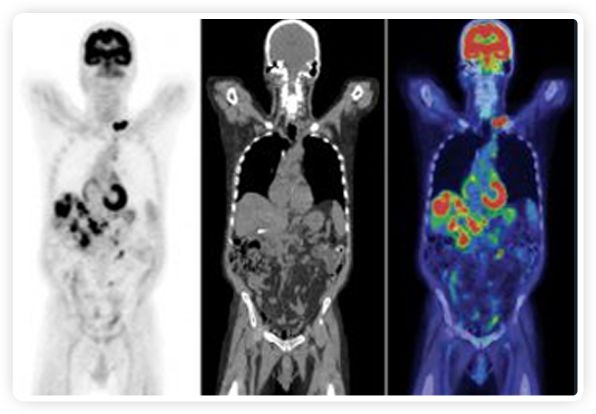

PET+放療共同治療

RefleXion將PET成像與立體定向放射治療相結(jié)合。在注射示蹤劑后,RefleXion的技術(shù)基于示蹤劑信號(hào)實(shí)時(shí)地在一個(gè)或多個(gè)目標(biāo)上引導(dǎo)治療性X射線。使用這種專有方法,RefleXion的平臺(tái)有可能比現(xiàn)有系統(tǒng)向癌癥病變提供更高劑量的輻射,并改善周圍健康組織的保護(hù)。